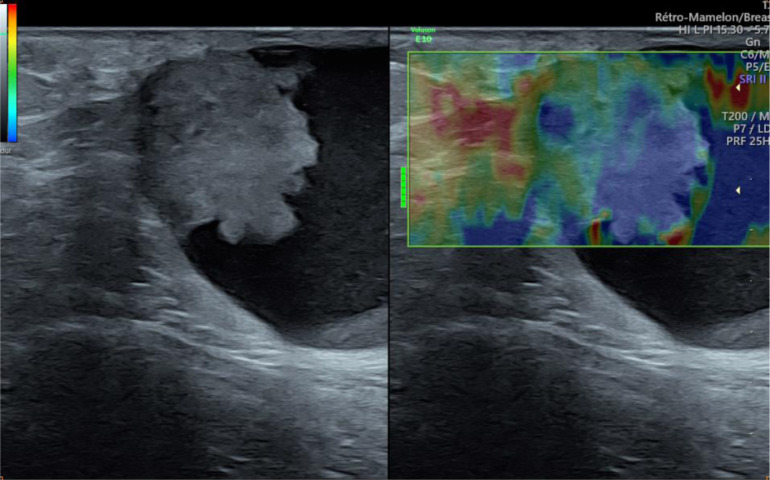

Ultrasonography was first performed showing a supernumerary breast tissue, of left axillary location, with a complex cystic mass containing an echogenic-anechoic liquid level, and a tissue component, that appears hyperechoic, with ill-defined margins, homogeneous (Fig. 2), with vascular pedicle in color Doppler (Fig. 3) and hard elasticity in ultrasound elastography (Fig. 4).

Fig. 4.

Ultrasound elastography showing hard elasticity of the tissue component.